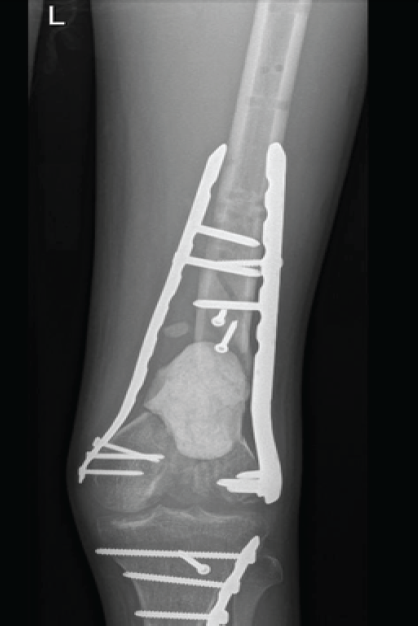

This patient is a 25-year-old female college student who was involved in a road traffic accident as a pedestrian struck by a motorcycle. She presented to the emergency department with a severe open fracture, with AO class: (AO 33-C3) (Fig. 1). The wound was a 15 cm laceration with exposed distal femur, patella, and lateral proximal tibial plateau.

Figure 1: Pre-operative anteroposterior and lateral radiographs showing a severely comminuted open distal femur fracture (AO/OTA 33-C3).

The distal 5 cm of the femur was severely comminuted. The preceding 10 cm showed a longitudinal split, with complete loss of the lateral aspect at the scene of the accident, while the medial aspect remained intact. Both femoral condyles were severely comminuted and no reconstrable.